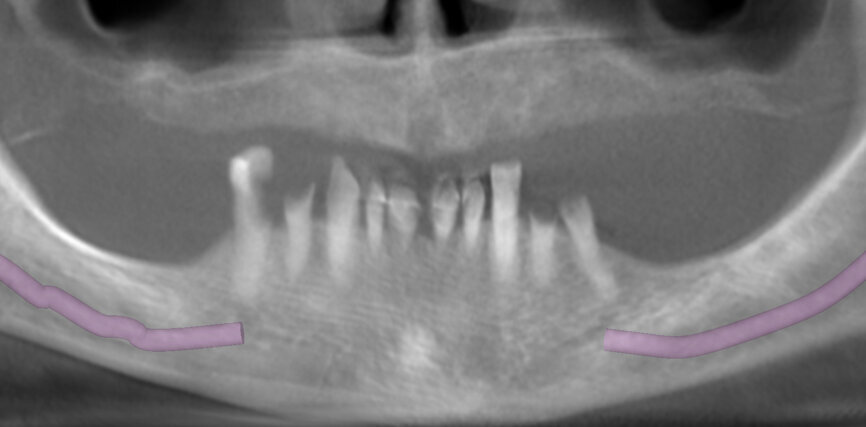

Bone quality in the mandible allowed placement of four implants in the anterior region, with both lateral implants tilted, and did not allow for any implants to be placed in the distal area. For these reasons, the Pro Arch concept was chosen as a treatment modality. As bone conditions in the mandible were very difficult in terms of correct implant placement, it was decided to place them with the help of a surgical guide.

The planning included several steps. First, the hopeless teeth in the mandible were to be extracted, followed by delivery of a complete immediate denture, as they did not offer any stable support for a surgical guide. Six weeks later, owing to the lack of keratinised tissue in the premolar regions, apical repositioning and a free gingival graft were performed (Fig. 2). After 1.5 months, the denture was relined with a mixture of barium sulphate and resin, transforming the denture into a radiographic stent (Fig. 3). Another CT scan was recorded with the stent in the mouth (Fig. 4). The stone cast of the stent was poured (Fig. 5), giving us the actual clinical picture of the mucosa, and both cast and stent were scanned to obtain their STL files. Using the coDiagnostiX planning software, the radiopaque saddle of the stent and the STL scan were matched, which also allowed the stent to be matched with the cast as positive and negative, thus, giving us the soft-tissue volume. Implants were planned in a prosthetically driven manner at sites #34, 32, 42 and 44, with corresponding screw-retained abutments (Fig. 6).